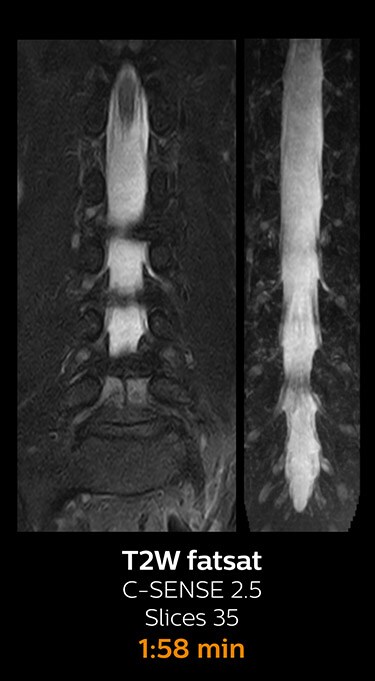

With Compressed SENSE, the scan time for the routine lumbar spine examination at KNC was reduced from 11:41 to 8:17 minutes,

MRI examination of the lumbar spine with Compressed SENSE

Ingenia 3.0T CX

Scan time 8:17 min. (was 11:41 min. without Compressed SENSE)